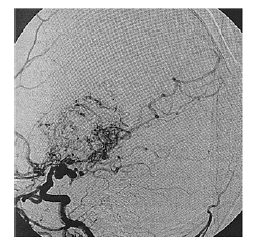

Paciente de 16 anos de idade, do sexo feminino, de asscendência japonesa, com deficits neurológicos progressivos iniciados ainda na infância, tem diagnóstico prévio de anemia falciforme. Realizou exame complementar de imagem do encéfalo, apresentado na reprodução acima. Há suspeita de doença de Moyamoya.